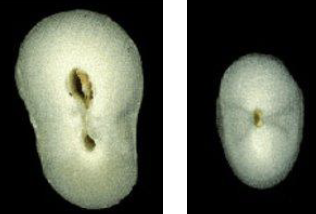

What is the anatomical variation in this lateral incisor?

Lingual developmental or palato-radicular groove